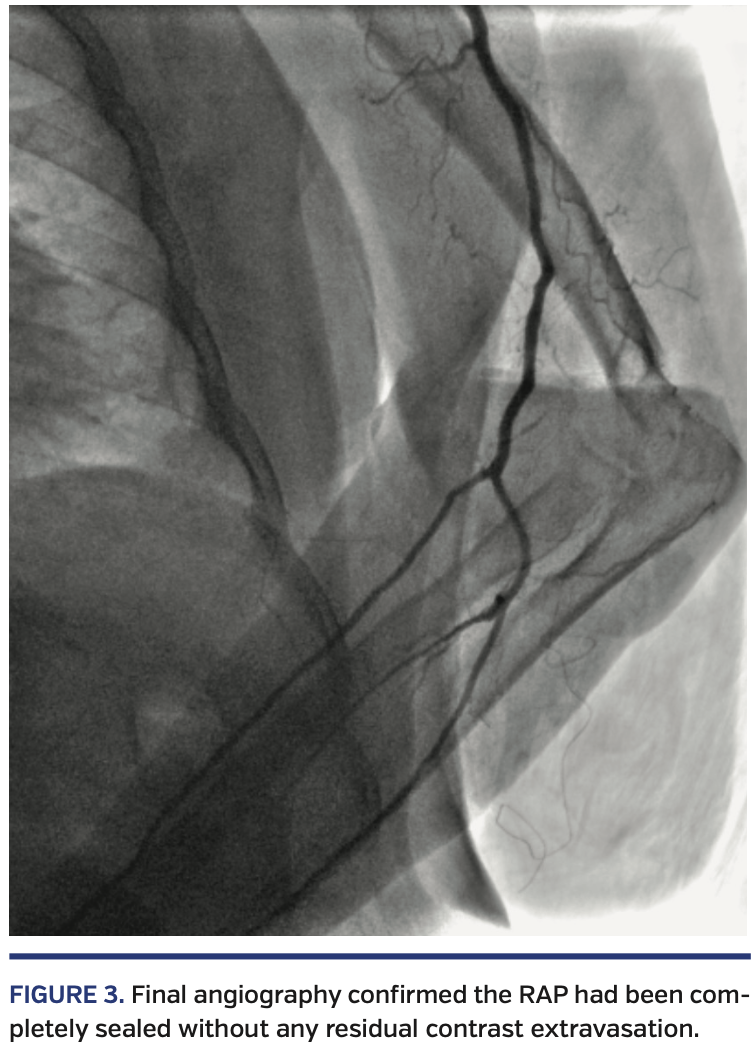

A 62-year-old woman with short stature, hypertension, diabetes, obesity, peripheral arterial disease, and previous acute myocardial infarction (AMI) requiring percutaneous coronary intervention (PCI) of the left anterior descending artery presented with non-ST elevation AMI. She was referred to urgent coronary angiography via left dTRA, using a 5/6 Fr hydrophilic slender Glidesheath (Terumo) inserted without any difficulties (Figure 1). Despite intra-arterial nitroglycerin, resistance was felt at the level of the forearm left radial artery (LRA), and it was not possible to further advance even a hydrophilic 0.035˝ J-tip wire through the LRA. Selective angiography (through the sheath) revealed severe LRA spasm and a large RAP with massive contrast extravasation (Figure 2; Video 1). The wire-crossing attempts always resulted in the false lumen; it was therefore decided to cross the site of perforation with a 5 Fr MP diagnostic catheter, without the rail of a wire, by gentle rotations and advancements. By confirming the normal arterial waveform pressure just proximal to the perforated area, the system was then carefully advanced up to the aortic root. The dominant right coronary artery (RCA) was diffusely diseased, with proximal-mid critical stenosis and a consequent Thrombolysis in Myocardial Infarction 2 flow (Video 2), without any significant lesions at the left coronary. The culprit RCA was promptly fixed by PCI with 3 drug-eluting stents (distal to ostial), requiring adequate pre- and postdilations and laborious reversion of an adenosine refractory no-reflow with papaverine (Video 3). By withdrawing the JR4 6 Fr guiding catheter, a final angiogram confirmed the perforation had been completely sealed without any residual contrast extravasation (Figure 3; Video 4). The patient was monitored for any signs of forearm compromise and uneventfully discharged home 2 days later.